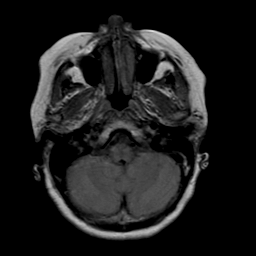

Stroke: proton density-weighted MR #2 -- Slice #3

[Home][Help][Clinical] Slice 3